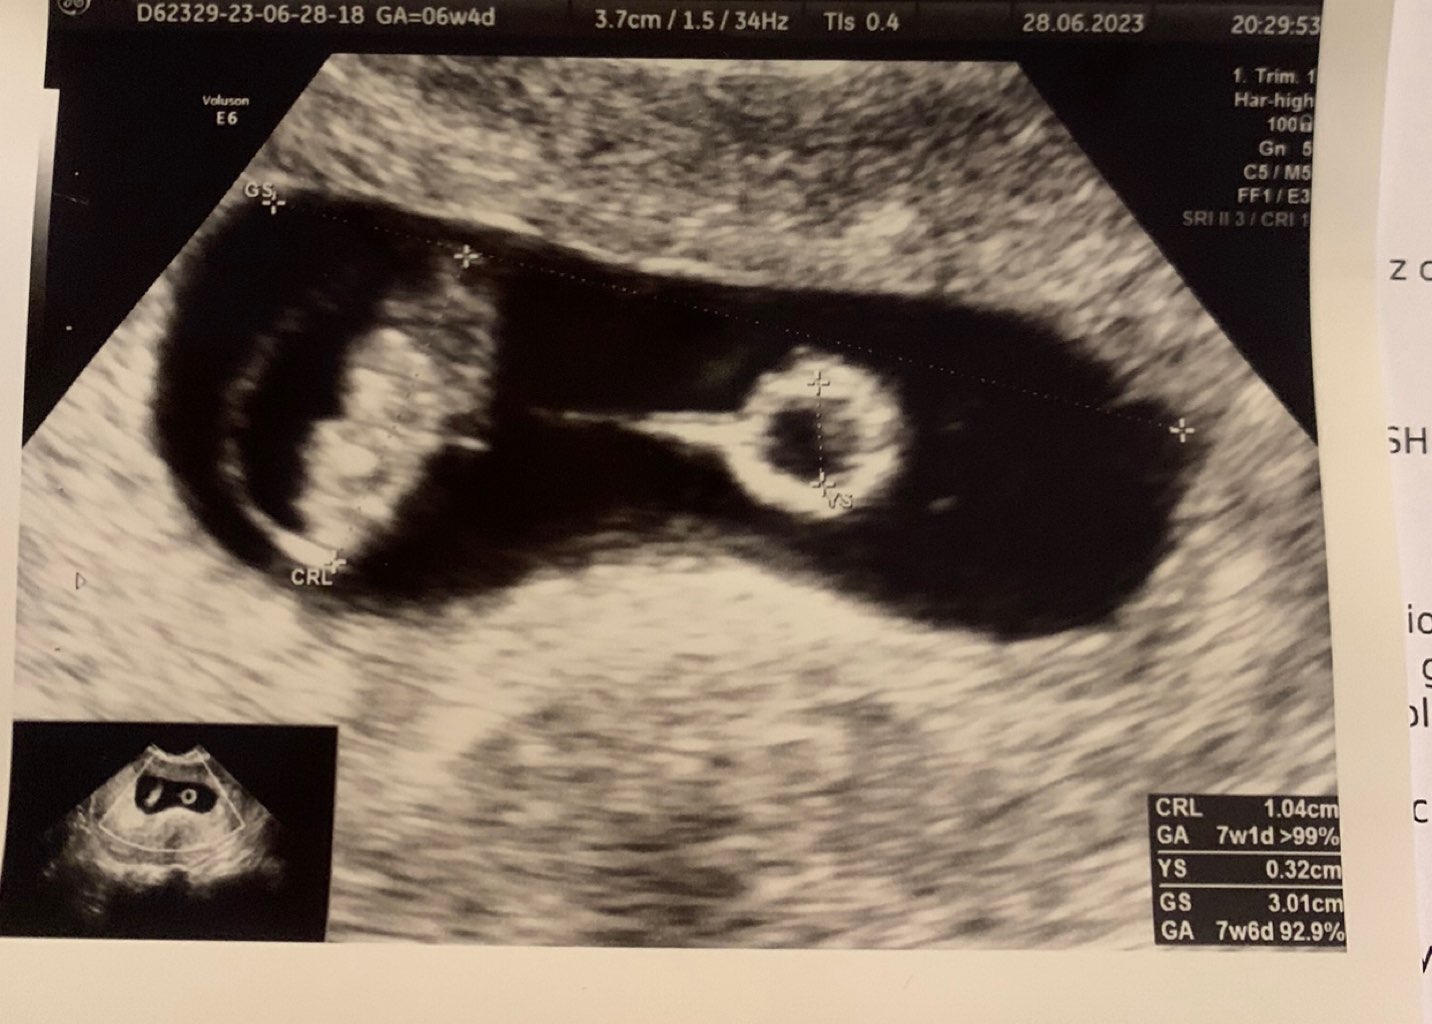

Ja jednak przyspieszyłam wizytę która miałam mieć w piątek i mamy serduszko♥️ kropek ma 1cm😀 serduszko bije 141😀 dziś 6+4tc a wg usg 7+1.

• IMG_9350.jpeg

IMG_9350.jpeg

172,6 KB · Wyświetleń: 70